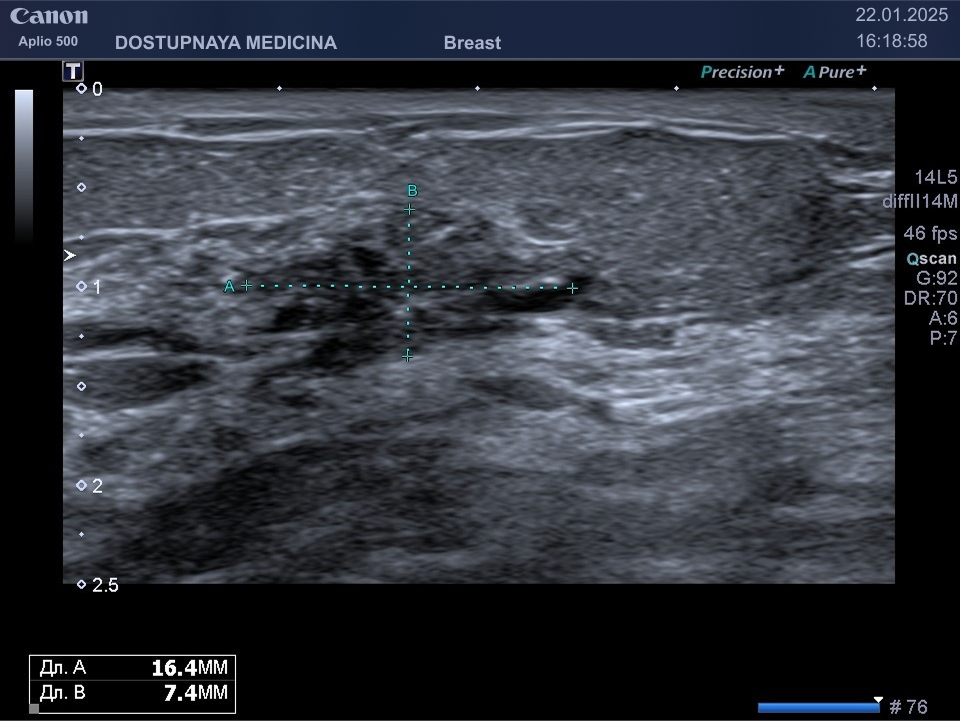

Следует проводить дифференциальную диагностику фиброаденомы с раком молочной железы, с кистой и с цистаденопапилломой. Поэтому важно повторить ультразвуковое исследование через 3 месяца, а затем при отсутствии тенденции к росту опухоли необходим УЗИ контроль через 6 месяцев.